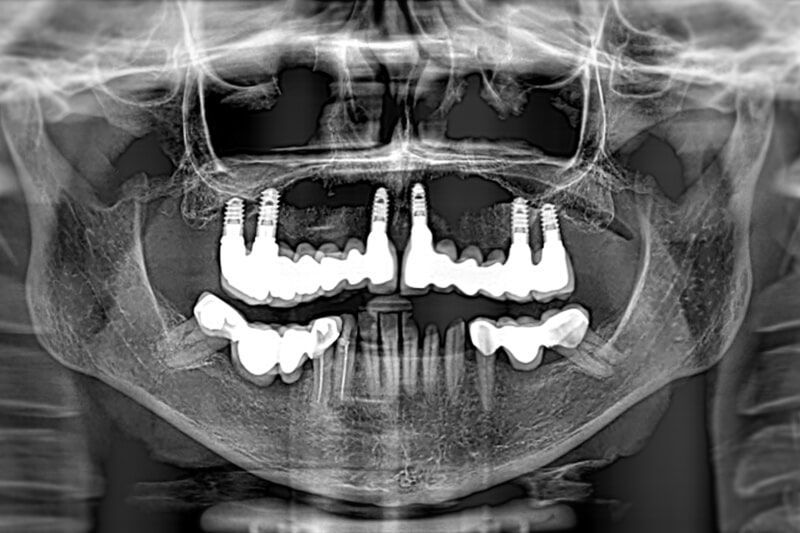

PATIENT WITH ATROPHY OF THE UPPER JAWBONE

Four zygomatic implants were placed under general anaesthesia with a prosthesis completely fixed to the implants in less than 24 hours.